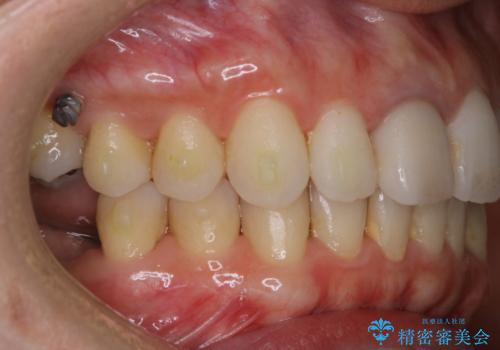

- インビザラインでのマウスピース矯正中にステインや着色を取りたいとのことでした。

PMTC60分コースを行いました。

PMTC(保険外治療)は、毎日の歯磨きで落としきれない汚れや、コーヒ、紅茶・タバコのヤニなどの着色も除去します。目には見えない歯と歯の間・歯肉の境目・インビザライン中はアタッチメント周囲などに残っているプラーク(歯垢)もしっかり取り除きます。PMTCでは専門的な機械や材料を使用して、徹底的に汚れを除去するため、虫歯・歯周病・口臭予防などにつながります。

またPMTCを行うことで、ご自身本来の歯の色になり自然な明るさになります。